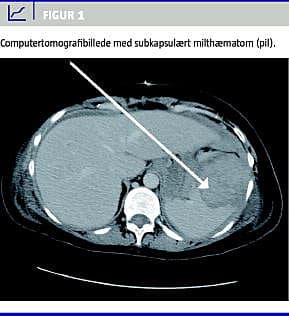

Under indgrebet blev der konstateret en større mængde såvel friskt som gammelt blod i abdomen, samt en tredjedel løsning af placenta. Da blødningskilden ikke kunne identificeres, blev den abdominalkirurgiske bagvagt tilkaldt. Under gennemgang af alle relevante strukturer blev der påvist en lille avulsion af miltens frie laterale kant. Der kunne ikke konstateres igangværende blødning, og fundet blev anført som et tidligere traume. Patienten var herefter somatisk stabil. Der blev foretaget CT med kontrast af thorax og abdomen, hvilket viste en grad III-miltskade, med et 5 × 7 cm intrasplenisk hæmatom og intakt kapsel (Figur 1 ).

Summary Relevant trauma in a haemodynamic stable patient should be computed tomographed in spite of pregnancy Ugeskr Læger 2012;174(17):1160-1161 A 37 year-old pregnant woman, gestational age 32 weeks, was involved in a motor vehicle accident. Abdominal ultrasound revealed no pathological findings, and the woman was discharged after 24 hours of observation. Three weeks later a healthy girl was delivered by emergency caesarean section due to placental abruption. During surgery a large amount of blood was detected and signs of previous trauma and haematoma to the spleen was revealed. Post-operative abdominal computed tomography scan was performed, revealing a 5 × 7 cm intrasplenic haematoma.